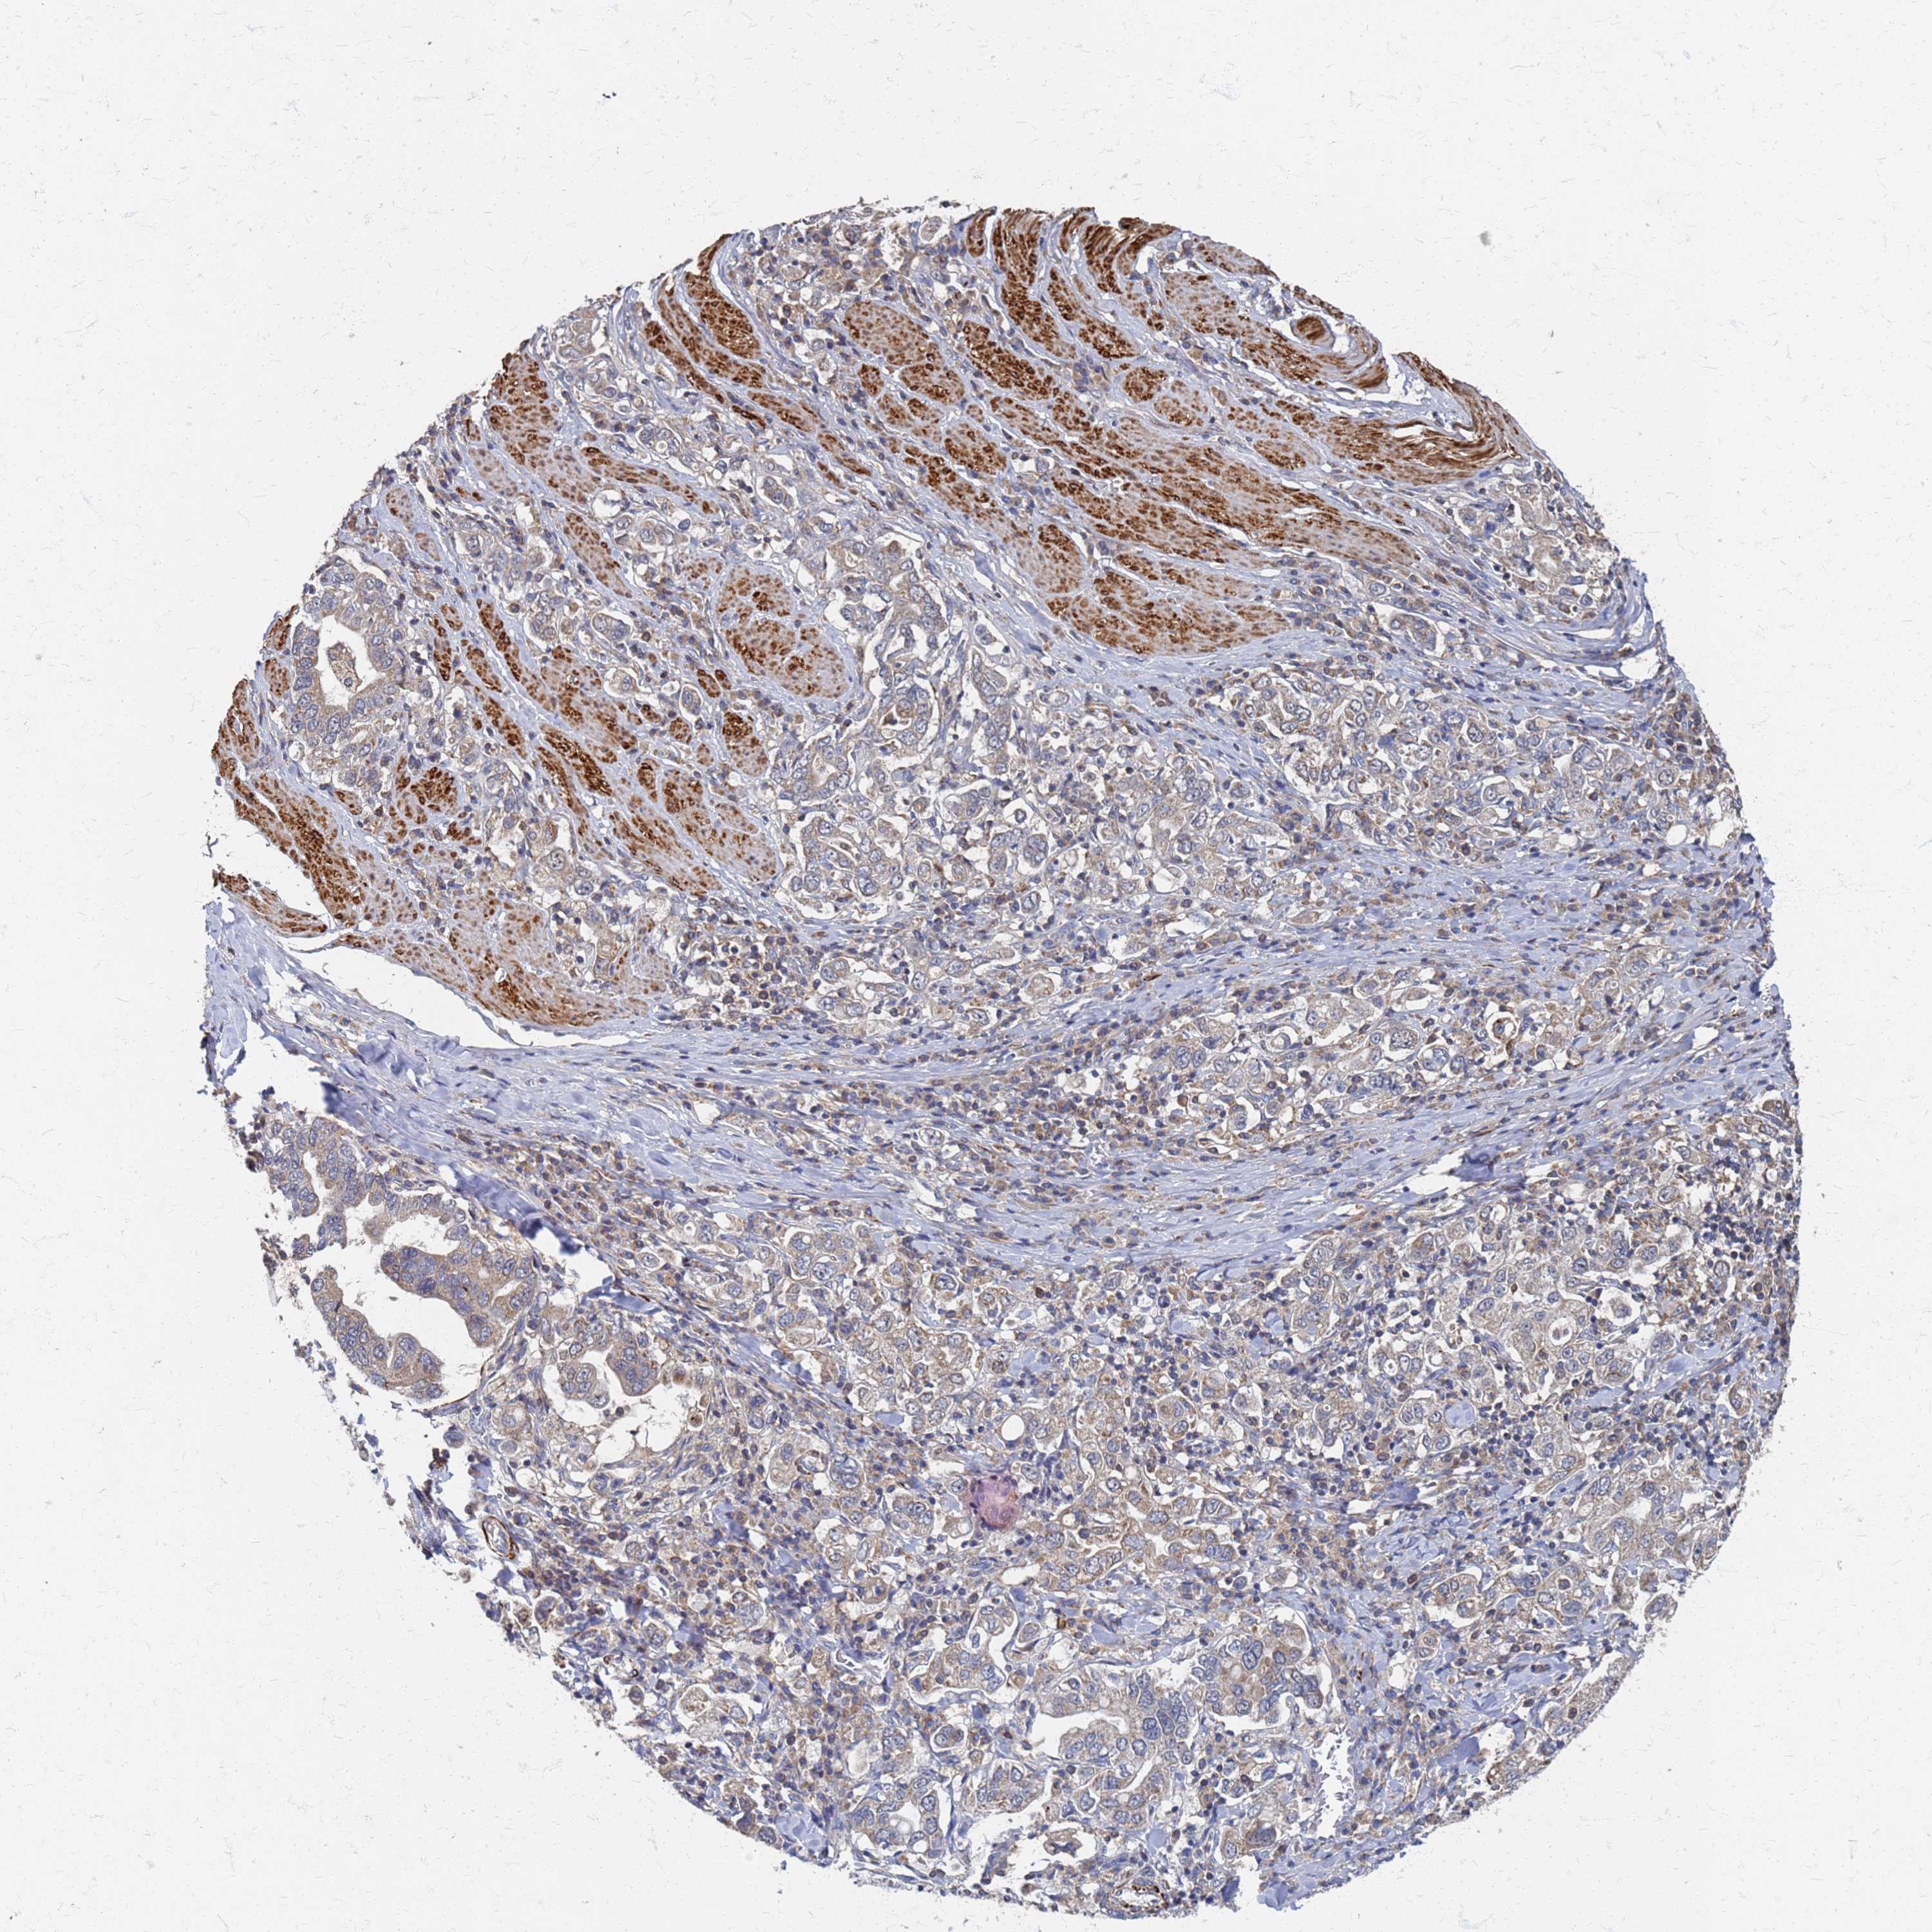

STOMACH CANCER - Protein expressioni

A mouse-over function shows sample information and annotation data. Click on an image to view it in a full screen mode. Samples can be filtered based on level of antibody staining by selecting one or several of the following categories: high, medium, low and not detected. The assay and annotation is described here.

Note that samples used for immunohistochemistry by the Human Protein Atlas do not correspond to samples in the TCGA dataset.

Antibody stainingi

Antibody staining in the annotated cell types in the current human tissue is reported as not detected, low, medium, or high, based on conventional immunohistochemistry profiling in selected tissues. This score is based on the combination of the staining intensity and fraction of stained cells.

Each image is clickable and will lead to virtual microscopy that enables deeper exploration of all samples and also displays staining intensity scores, fraction scores and subcellular localization as well as patient and tissue information for each sample.

Antibody HPA044950

Staining

High

Medium

Low

Not detected

Intensity

Strong

Moderate

Weak

Negative

Quantity

>75%

75%-25%

<25%

None

Location

Nuclear

Cytoplasmic/membranous

Cytoplasmic/membranous,nuclear

Adenocarcinoma, NOS